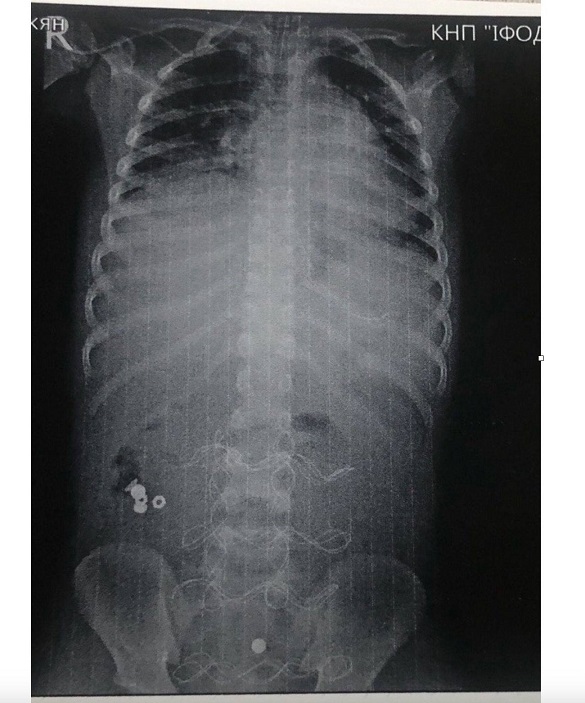

До ОДКЛ Івано-Франківська привезли 7-річного хлопчика у вкрай тяжкому стані інфекційно-токсичного шоку з клінікою розлитого перитоніту.

«Як виявилось, все через батарейку, яку дитина проковтнула, що спричинило перфорацію тонкого кишківника. 12 годин тривала передопераційна підготовка. Всього було проведено 3 оперативних втручання і лише на 20 добу дитину було виписано в задовільному стані. Обов'язково поясніть дітям можливі наслідки ковтання батарейок, магнітів та інших предметів не призначених для цього!», - зазначив генеральний директор медзакладу Тарас Мельник.